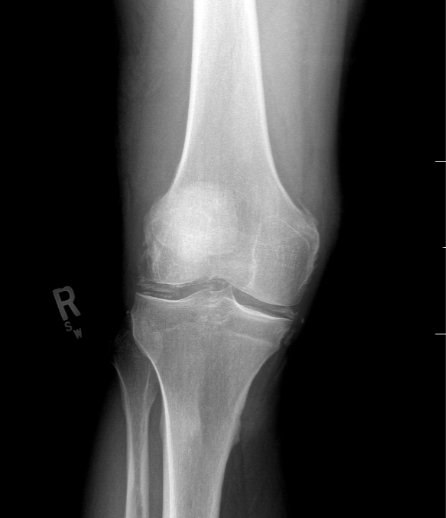

A 53-year-old male presented with worsening right knee pain and swelling over the past 48 hours. He denied recent trauma to the knee, history of IV drug use, and recent illness. He had no history of diabetes, immunodeficiency, chronic steroids, rheumatologic disease, or knee replacement. He described the pain as sharp, non-radiating, and worse with movement. He was unable to walk due to pain.

Radiographs of the knee showed multiple radio-dense lines paralleling the articular surface (see red arrows) consistent with calcium pyrophosphate crystal deposition within the joint often seen in calcium pyrophosphate disease (CPPD) also known as pseudogout.

Patients commonly present to the emergency department with non-traumatic joint pain. Arthrocentesis is an important diagnostic tool to evaluate for septic arthritis, gout, or pseudogout. Arthrocentesis can demonstrate crystals or abnormal cell count, gram stain, and culture.[1] In the evaluation of joint pain, plain films are usually obtained to evaluate for fracture, dislocation, effusion, or secondary signs of infection. In this case the classic x-ray supported the diagnosis of CPPD.2 The patient was found to have positively birefringent rhomboid shaped crystals consistent with pseudogout on arthrocentesis. Gram stain and culture were both negative. The patient was discharged with NSAIDs and had significant improvement in symptoms upon follow up with primary care physician in 3 days.